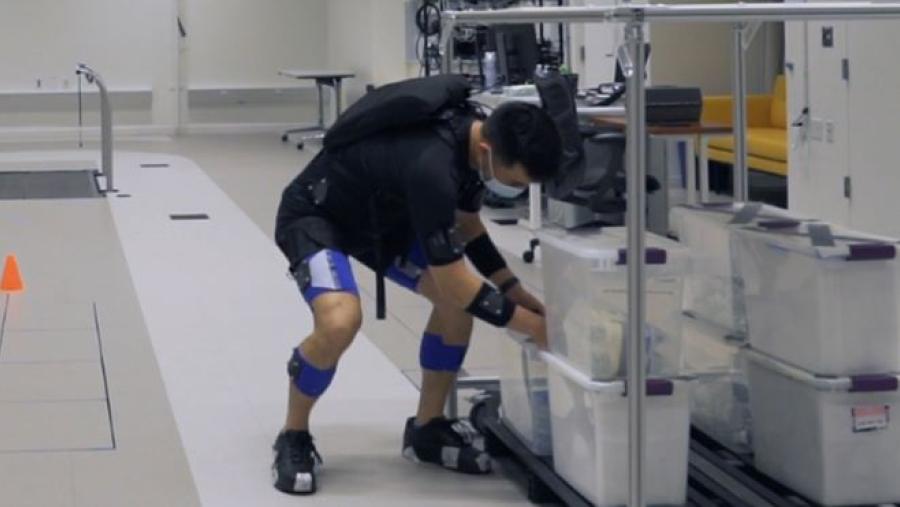

Image

“Artificial muscle” may help prevent back problems

Published: June 6, 2022